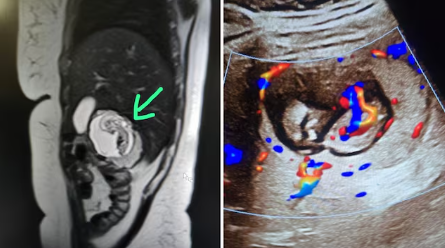

“When I saw the scan, I could not believe my eyes. The foetus was embedded in the right lobe of the liver, and there were clear cardiac pulsations. I have never seen such a case in my career, and according to available data, this might be India’s first intrahepatic ectopic pregnancy,” said Dr KK Gupta, a radiologist at a private imaging centre in Meerut, who uncovered it while carrying out the MRI abdomen test of the woman.

According to Dr Gupta, the scan revealed a startling anomaly. “We observed a well-formed gestational sac inside the right lobe of the liver. The foetus measured approximately 12 weeks in gestational age. Most strikingly, the scan confirmed active cardiac pulsations, establishing that the foetus was alive. At the same time, the uterus was completely empty, ruling out a normal intrauterine pregnancy,” Dr Gupta explained.

He further detailed that the foetus appeared embedded deep into the parenchymal tissue of the liver, with blood vessels from the organ supplying nutrition to the sac. This confirmed that the pregnancy had implanted directly into the hepatic tissue — an occurrence almost unheard of in India.

Dr Gupta also said that the diagnosis was double-checked by repeating certain MRI sequences to rule out imaging errors. “Initially, I even thought it might be an imaging artifact. But repeated scans, taken from different planes, confirmed the presence of a live foetus within the liver tissue itself. At that moment, we realised we were dealing with an extremely rare, high-risk pregnancy,” he added.